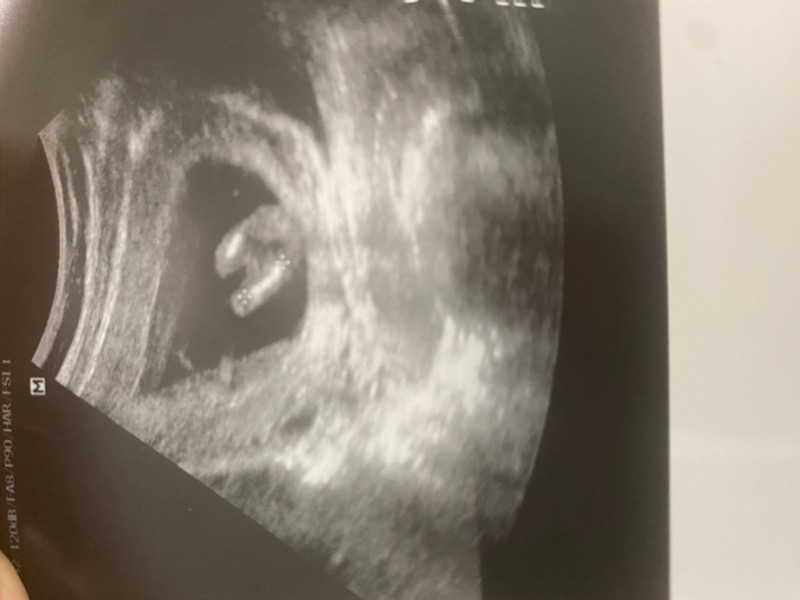

بنات وش تتوقعون واضح الالا ؟

باين ولد ما شاء الله عليه الله يجيبلك بخير وسلامة 💙

الحمدالله كل شي تمام بس جنين في وضع سجود ولله حول دكتور وقال ان شاء الله ولد يعنى مهو كيد بسبب وضع جنين